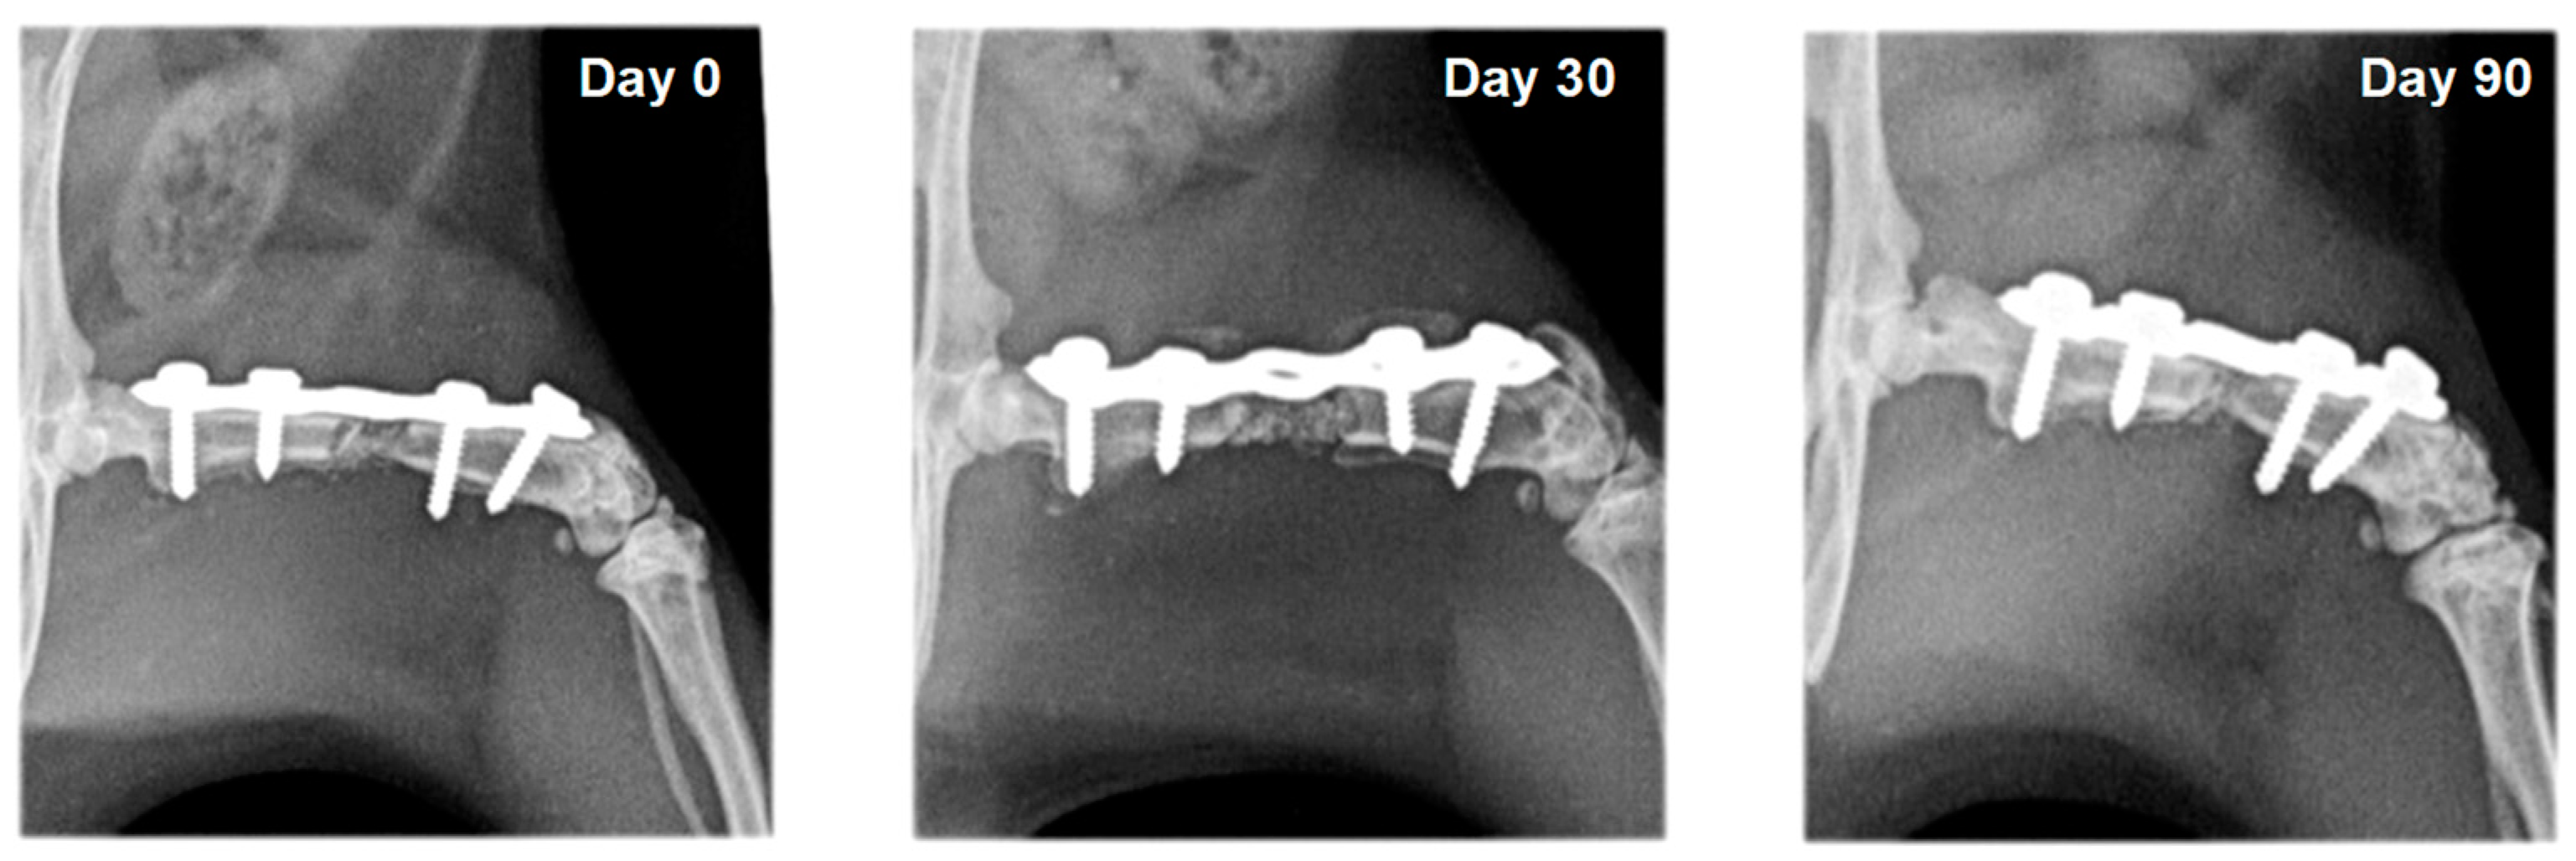

In rats whose defects were filled with bone substitute, the xenograft was visualized with strong heterogeneous radiopacity and was radiologically visible until the end of the experiments. Bone integration between the xenograft and the host bone was not observed in rats from group F5, which were treated with bone substitute and saline. Bone formation was evident in animals from group F6, whose defects were filled with bone substitute and erythropoietin (Figure 7 and Figure 8). A statistically significant difference (p < 0.05) between the healing scores of these two groups was observed on the 30th post-operative day (Table 1).

Figure 7.

Serial craniocaudal radiographs of rat femurs from experimental group F5 on post-operative days 0, 30 and 90.

Figure 8.

Serial craniocaudal radiographs of rat femurs from experimental group F6 on post-operative days 0, 30 and 90.